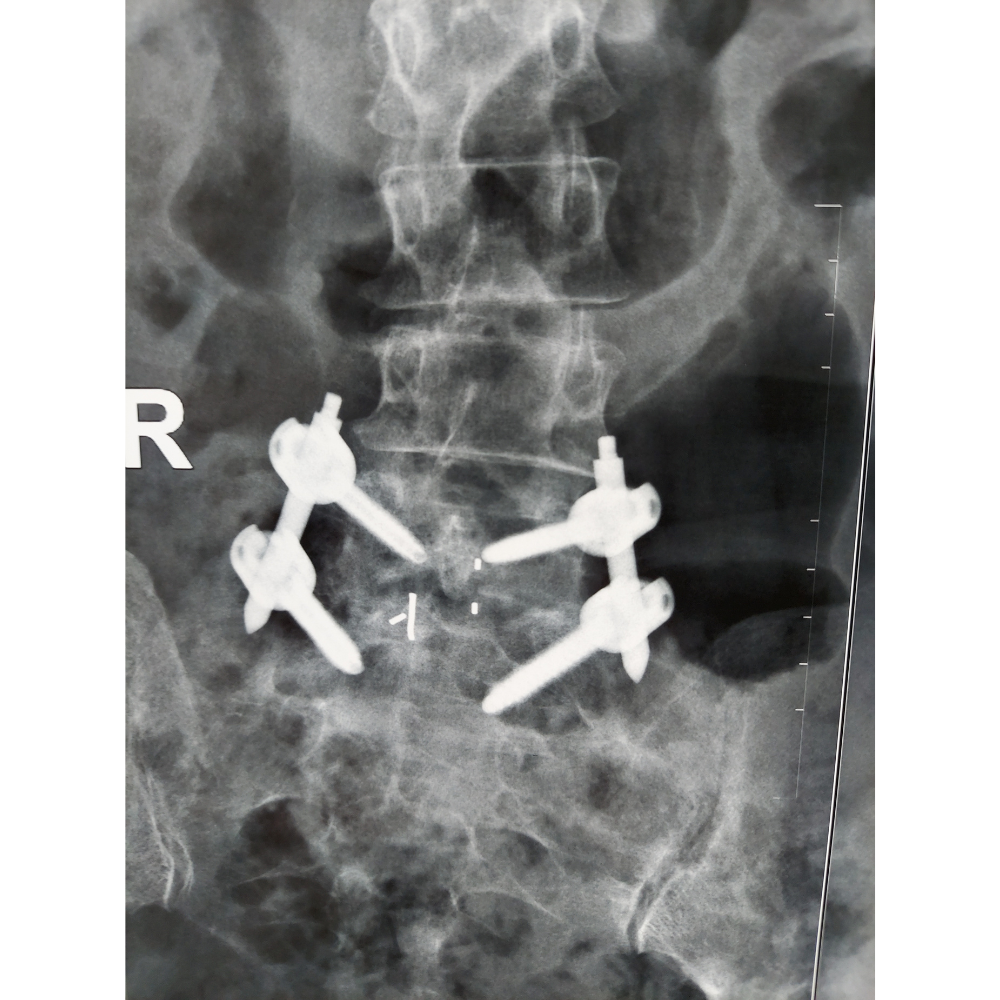

3. Disc Removal and Fusion: The damaged disc tissue is removed, and the intervertebral space is prepared for fusion. Bone graft material, often taken from the patient’s own body or a bone bank, is inserted into the disc space to promote fusion.

4. Implant Placement: Metal screws and rods may be inserted into the vertebrae to provide additional stability and support. These implants help maintain proper alignment and facilitate fusion of the affected vertebrae.

5. Closure: The incisions are closed with sutures or surgical staples, and a sterile dressing is applied to the surgical site.